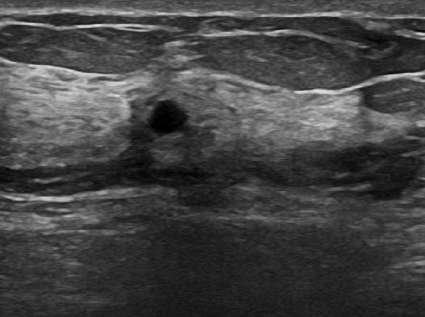

4.1.4 Ultrasound breast cancer

Breast cancer has gained significant attention in recent times due to its high mortality rate and the increasing number of reported cases. Using the ultrasound imaging technique makes it possible to observe the tissue distribution for cancer visual detection, making it an early detection alternative to diminish the public health impact. The dataset444https://www.kaggle.com/datasets/sabahesaraki/breast-ultrasound-images-dataset used in this work contains 780 images with three categories: benign with 442 images, malignant with 206, and normal with 132. The scans were collected from 600 women between 25 and 75 years old. It is a highly unbalanced dataset with different image sizes, having an average of 500×500500500500\times 500500 × 500 pixels [38]. Figure 5 showcases examples from each of the three described classes.

Refer to caption

(a) Normal

(b) Benign

(c) Malign

Figure 5: Breast ultrasound images.